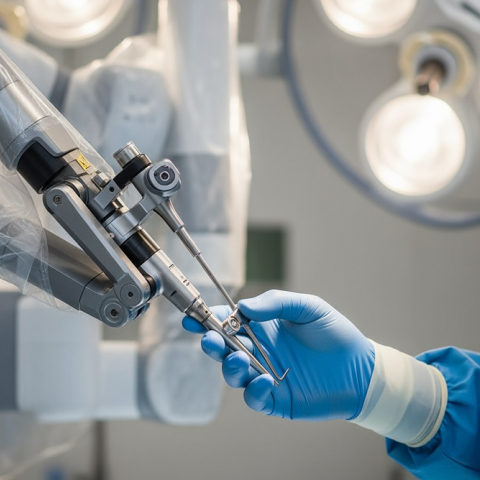

Τα δεδομένα στο Άσθμα και στη Χρόνια Αποφρακτική Πνευμονοπάθεια (Χ.Α.Π) έρχεται να αλλάξει νέα θεραπεία που κυκλοφορεί πλέον και στην Ελλάδα, προσφέροντας στους ασθενείς μια πιο φυσιολογική ζωή. Πρόκειται για τον πρώτο σταθερό συνδυασμό εισπνεόμενου κορτικοστεροειδούς και βρογχοδιασταλτικού που προσφέρει συνεχή 24ωρη αποτελεσματικότητα στον ασθενή με μία ημερήσια δόση (εισπνοή), από μια εξελιγμένη και πολύ εύχρηστη συσκευή.

Την κυκλοφορία της νέας θεραπείας, η οποία αποτελεί συνδυασμό του εισπνεόμενου κορτικοστεροειδούς (ICS), φουροϊκής φλουτικαζόνης, και του β2-αγωνιστή μακράς δράσης βιλαντερόλη ανακοίνωσε η GSK. Για την αντιμετώπιση του άσθματος έχουν λάβει έγκριση δύο δοσολογικά σχήματα (92/22 mcg και 184/22 mcg), ενώ για την αντιμετώπιση της ΧΑΠ το δοσολογικό σχήμα 92/22 mcg.

Στο πλαίσιο της αξιολόγησης προς έγκριση αυτής της νέας θεραπείας, ο Ευρωπαϊκός Οργανισμός Φαρμάκων είχε στη διάθεσή του τα αποτελέσματα 11 κλινικών μελετών σε 7.851 ασθενείς με ΧΑΠ και 16 μελετών σε 9.326 ασθενείς με Άσθμα.

Η Τζούλια Βασιλειάδου, ιατρική διευθύντρια της GSK Ελλάδας, υπογράμμισε: «Η κυκλοφορία του πρώτου σταθερού συνδυασμού εισπνεόμενου κορτικοστεροειδούς και βρογχοδιασταλτικού που προσφέρει συνεχή 24ωρη αποτελεσματικότητα στον ασθενή με μία ημερήσια δόση, αποτελεί ορόσημο για τον ασθενή που πάσχει από Άσθμα ή Χρόνια Αποφρακτική Πνευμονοπάθεια. Το αίσθημα της δύσπνοιας και οι παροξύνσεις της νόσου που βιώνει ο ασθενής είναι εξαιρετικά δυσάρεστες και για την αντιμετώπισή τους μπορεί να χρειαστούν ακόμα και νοσηλείες στο νοσοκομείο, επιβαρύνοντας αρνητικά τον ίδιο, την οικογένειά του αλλά και το σύστημα υγείας. H νέα θεραπεία έρχεται να αλλάξει τα δεδομένα στο Άσθμα και τη ΧΑΠ, δίνοντας τη δυνατότητα στους ασθενείς να απολαμβάνουν μια πιο φυσιολογική ζωή, χωρίς περιορισμούς από τη νόσο τους. Τα καινοτόμα μόρια 24ωρης δράσης της νέας θεραπείας προσφέρουν την αποτελεσματικότητα που ο ασθενής χρειάζεται στη διάρκεια του 24ώρου, με μια μόλις εισπνοή την ημέρα, σε μια εξελιγμένη και ιδιαιτέρως εύχρηστη συσκευή. Επιπλέον, η συγκεκριμένη θεραπεία προσθέτει στη φαρέτρα των επαγγελματιών υγείας ένα θεραπευτικό σχήμα το οποίο μπορεί να βελτιώσει σημαντικά τη συμμόρφωση των ασθενών στη θεραπεία».